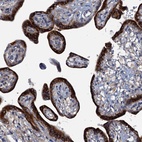

Immunohistochemical staining of human placenta shows strong cytoplasmic positivity in trophoblastic cells.